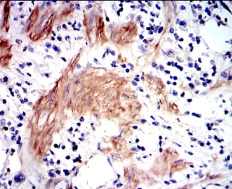

GSTM1 Mouse Monoclonal antibody[1H4F2]

IHC    1/200 - 1/1000